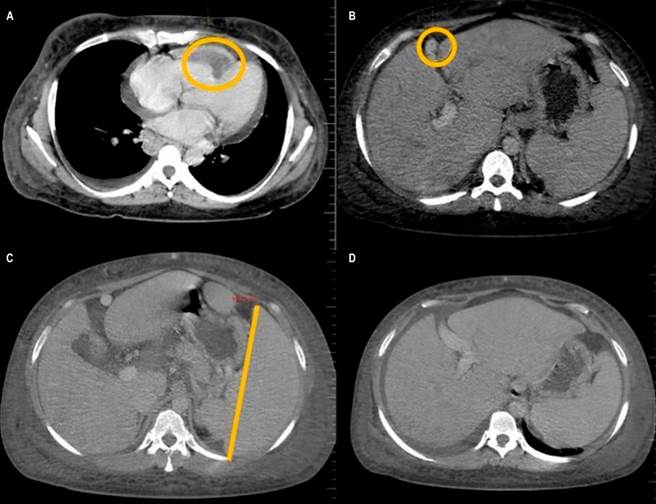

De acuerdo con el protocolo de pandemia por COVID-19, se le realizó un hisopado nasofaríngeo basado en la técnica de reacción en cadena de polimerasa (PCR), la cual fue positiva. La tomografía axial computarizada (TAC) contrastada de abdomen reveló consolidaciones en el lóbulo inferior derecho con derrame pleural, aurícula derecha dilatada, trombosis del ventrículo derecho (VD), vía biliar intra- y extrahepática conservada, vesícula biliar normal, sin litiasis. Se evidenció SBC por ausencia del flujo sanguíneo a nivel del tracto de salida de la vena suprahepática media, hipertensión portal, circulación colateral, hepatomegalia, esplenomegalia, ascitis y adenomegalias de predominio inguinal (Figura 1).

Figura 1 TAC contrastada que revela: A. Trombosis de la aurícula derecha; B. SBC evidenciada por ausencia del flujo sanguíneo a nivel del tracto de salida de la vena suprahepática media, hepatomegalia; C y D. Esplenomegalia, ascitis y circulación colateral. Cortesía del departamento de radiología del Hospital Regional de la Orinoquia (HORO).